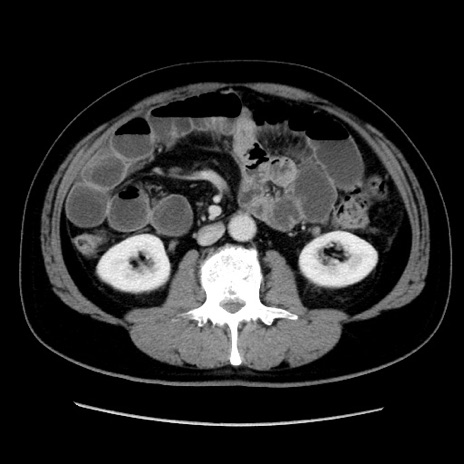

症例16(横断像)

【症例】 70歳代男性

【主訴】 腹痛、嘔吐

【現病歴】 約1ヶ月前より間欠的に腹痛と嘔吐あり、当院消化器内科を受診したところCTで多発する肝臓のLDAを指摘され、精査中であった。以降は消化器症状は安定していたが、2日前より嘔気と腹痛があり、同日より排便・排ガスが消失した。改善認めず、 本日、救急外来を受診した。

【身体所見】意識清明・会話良好、BT 36.3℃、BP 127/80mmHg、 P 80bpm、腹部:膨満あり、平坦・軟、上腹部正中および下腹部正中に圧痛あり、反跳痛なし、筋性防御なし。

【データ】WBC 7200、CRP 0.77